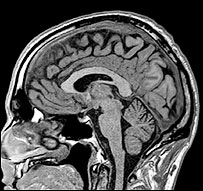

儿童脑部扫描

儿童脑部扫描发现神经纤维大量增加

扫描显示,他们的脑袋在短短三个月内经历了一般需要三年时间的发育。

不过,最让科学家惊异的是脑部的扫描结果。

高量的NAA等于有更多神经纤维在脑部生长。领导这项研究的伦敦帝国学院(Imperial College)的普里教授(Professor Basant Puri)说:“结果令人惊讶。在三个月内,原本只有少量NAA增长。但是我们看到了需要三年时间才出现的增长。”

他说:“这等于说,他们的脑部的神经细胞有更多连接,也更密集。”

这些增长出现在整个大脑皮层,也就是脑部的“思想区”。